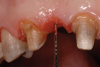

A patient presented with two defective 3-unit fixed partial dentures spanning teeth Nos. 6 through 8 and teeth Nos. 9 through 11 (Figure 7). The defective fixed partial dentures were removed (Figure 8), an impression was made, and traditional provisional fixed partial dentures without ovate pontics were placed. After the impression was sent to the laboratory, the lab technician prepared ovate pontic sites on the stone cast (Figure 9) and fabricated the new definitive bridges. On the day of insertion, the provisional fixed partial dentures were removed (Figure 10), ovate pontic sites were prepared using a teardrop-shaped diamond bur (Figure 11), and the sites were sounded to confirm that there was at least 2 mm from the base of the pontic site to the alveolar bone (Figure 12). The fixed partial dentures were cemented, and the postoperative healing was uneventful (Figure 13).

(10.) Close-up view of the existing edentulous tooth No. 10 site prior to the creation of the ovate pontic site.

Figure 10